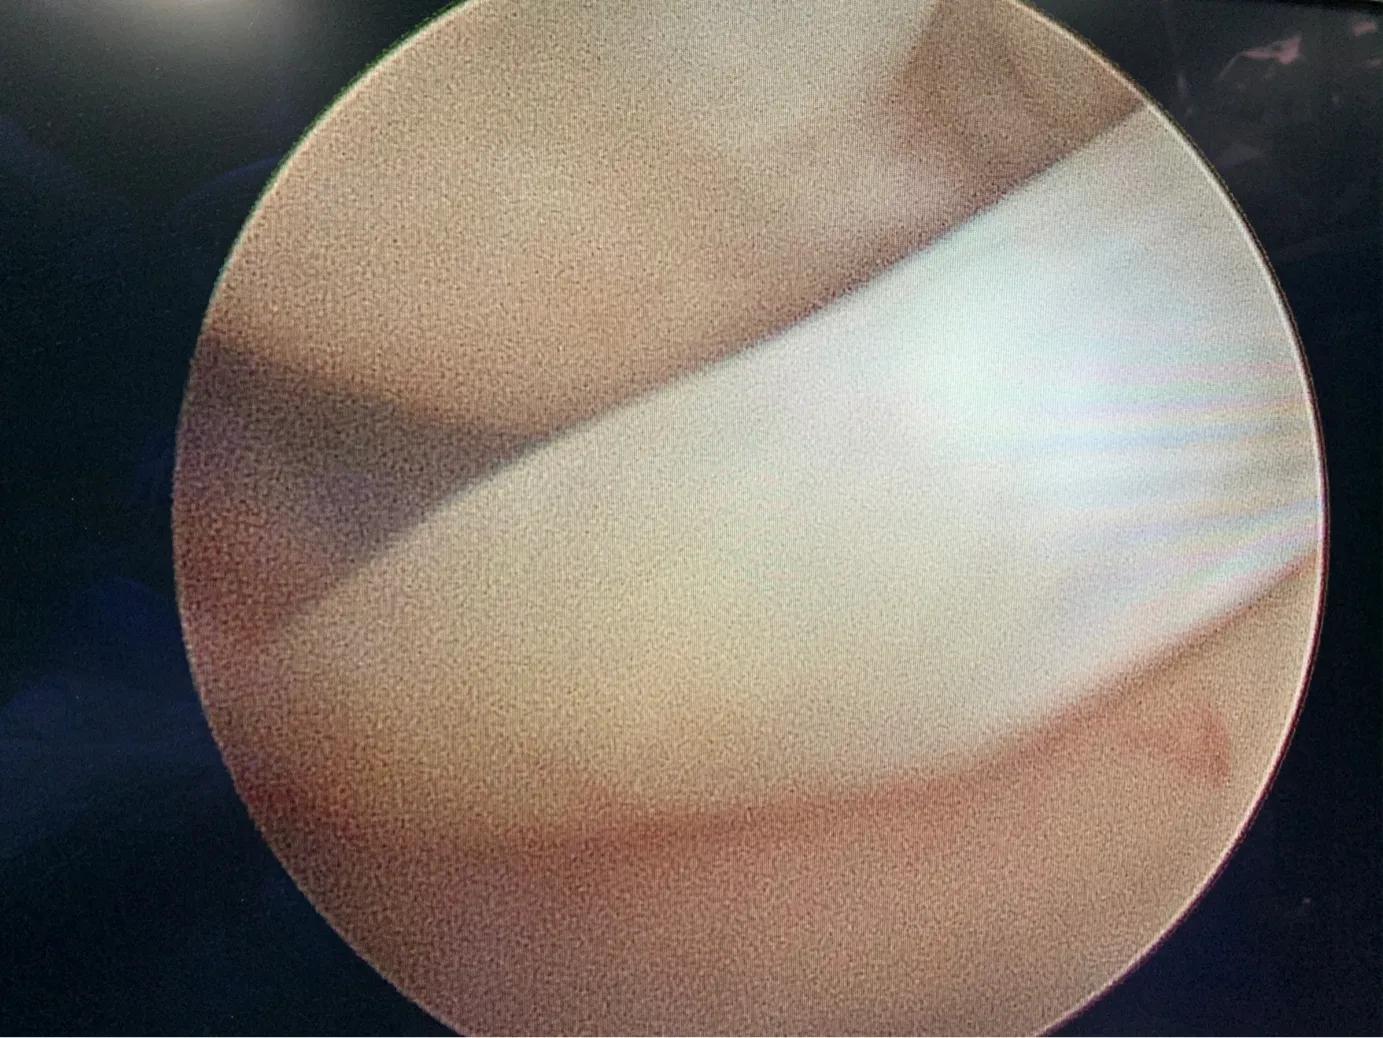

关节镜下看到的半月板损伤